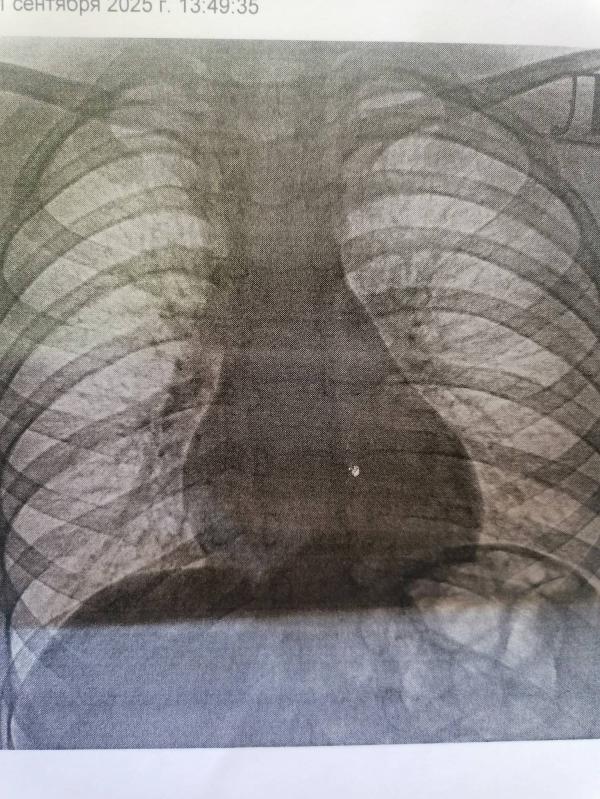

Распечатку на бумаге никто оценить не сможет. Либо рентген снимок к окну приложить, а вам его не дали раз распечатку показываете, либо ждать пока рентгенолог опишет. Здесь можно сказать что легочный рисунок усилен, особенно справа.

По одному рентгену невозможно точно сказать: это именно пневмония или другая причина. На рентгенограмме есть подозрительный участок затемнения в правом лёгком, который может соответствовать пневмонии, но надо смотреть и кровь, и клинику.